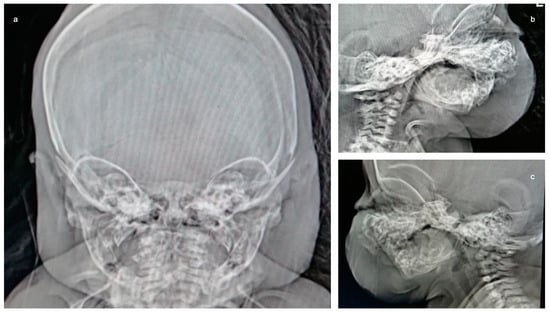

The following tests were carried out: brain ultrasound, skull X-ray, and head and neck CT scan. The brain ultrasound showed an enlargement of the third ventricle, and the corpus callosum was not detectable; since the examination was performed with an inappropriate probe (only the adult convex probe was available), it was not possible to visualize the cerebral cortex (Figure 3). On the skull X-ray, complete disorganization of the axillary and mandibular bones was revealed (Figure 4). To understand the malformation more precisely, a cranial CT scan was performed, which clarified the picture of bony disorganization of the maxillofacial complex; this examination revealed the presence of duplication of the mandible and, partially, the maxillary bones and the presence of a double opening of the oral cavity (Figure 5). Through CT image analysis of the central nervous system, it was possible to confirm the agenesis of the corpus callosum and the presence of a small anterior midline lipoma, a small posterior cranial fossa with the extension of the tonsils beyond the level of the foramen magnum was also found (Chiari I malformation) (Figure 6).

Figure 4. X-ray of the skull: On both the AP image and the lateral projections, it is difficult to recognize the duplication of the maxilla and mandible. The coronal and sagittal sutures are wide.